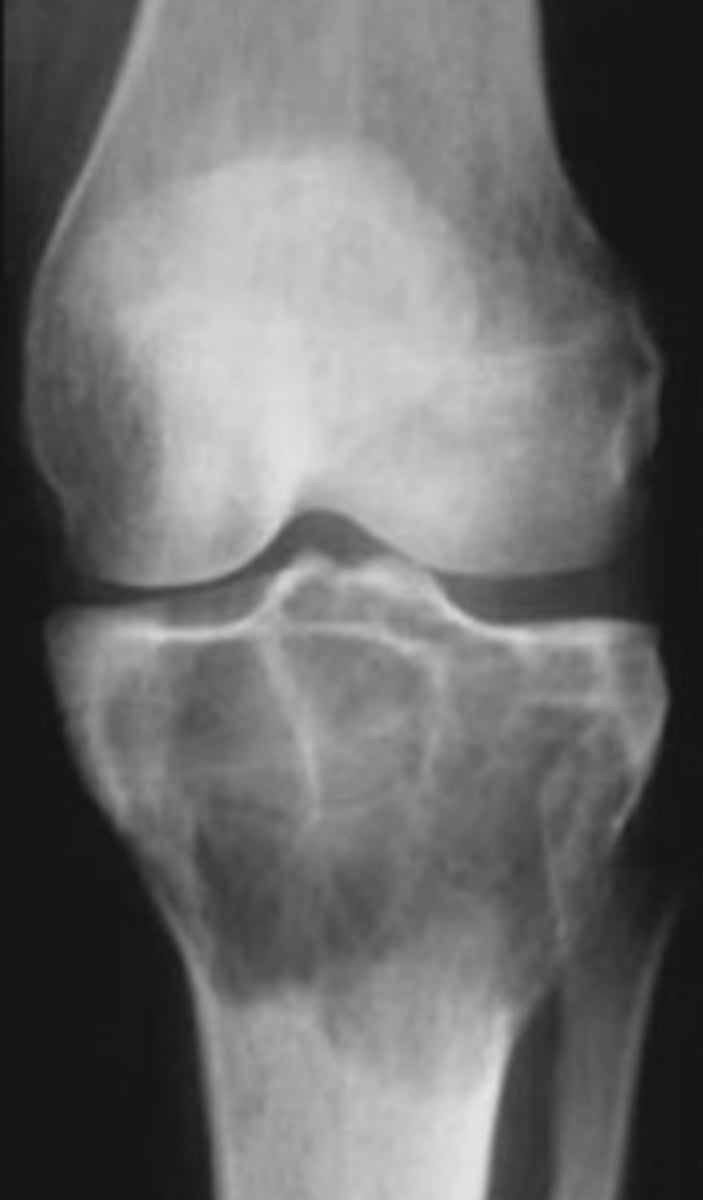

Osteoclastoma

Another term for giant cell tumor

- 80%

- 20%

Giant cell tumor pathology:

- _____ benign (F:M, 3:2)

- _____ malignant (M:F, 3:1)

- 20-40 y.o.

- Knee (tibia and femur)

- Localized pain and aching

- Joint pain and restricted motion

State the clinical features of giant cell tumor

- Osteolytic

- Geographic

- Multiloculated and septated

- Begin in metaphysis

- Extend to subarticular bone

- Expansion

- Eccentric

- Quasi-malignant (can't tell benign from malignant)

State the imaging features of giant cell tumor

Biopsy

We need to do a _____ to tell if giant cell tumor is benign or malignant